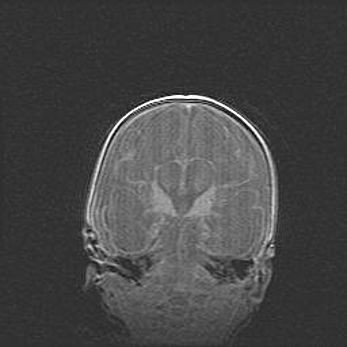

Наружная гидроцефалия с возможной атрофией височных областей.

Возраст: 28 дней

Вес: 3670 г

Пол: мужской

Окружность головы: 38 см

Срок гестации: 40 недель

Гидроцефалия головного мозга у новорожденных – это заболевание, которое характеризуется скоплением избыточного количества спинномозговой жидкости в желудочковой системе головного мозга в результате затруднения её перемещения от места выработки к месту поглощения в кровеносную систему или вследствие нарушения абсорбции. При открытой наружной форме гидроцефалии у новорожденных расширяются и переполняются субарахноидные пространства.

При нормотензивных  формах,  которые,  как  правило,  являются  следствием  перенесенных ишемических  повреждений  паренхимы  мозга,  возможно  сочетание микроцефалии  с нормотензивной гидроцефалией. В основе данных изменений лежит атрофия больших полушарий с преимущественной  локализацией  в  лобно-височных  областях.